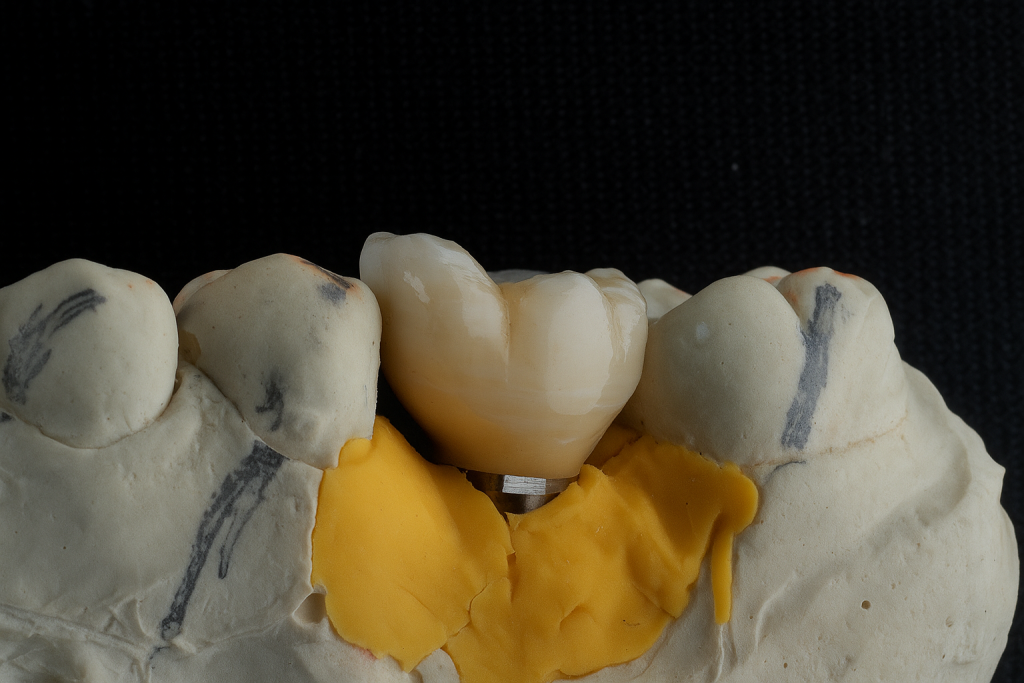

A precision-milled titanium base abutment was torqued to the manufacturer’s specification. The abutment contour was selected to promote a natural gingival transition and preserve the mucosal seal.

3. Crown Fabrication

A monolithic zirconia prosthesis was fabricated with precise occlusal morphology and central screw access for retrievability. The restoration was individually characterised and glazed to reproduce enamel texture and hue harmony with adjacent teeth.

3️⃣ Titanium base and crown assembly